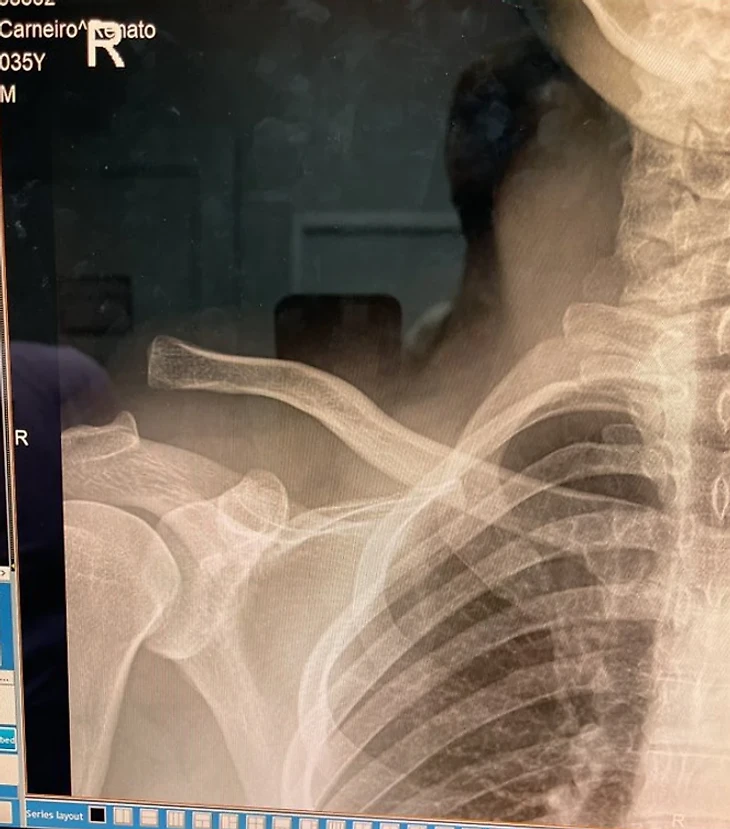

Мойкано получил серьезную травму за несколько недель до поединка с Сен-Дени.

«Я повредил плечо три недели назад, но не смог сняться с главного события... Спасибо моей команде за помощь в тренировках и за то, что подготовили меня к бою», – написал в соцсетях боец.